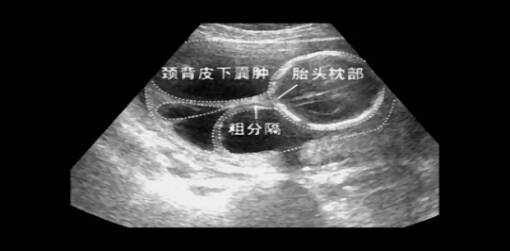

在超声检查中,医生可能发现一个多囊性包块,通常位于颈部附近,但也可以存在其他地方,如:腋窝、腹部或下肢。

胎儿颈部水囊状淋巴管瘤在孕期缺乏有效治疗方法,部分患者可在超声引导下行宫内囊肿穿刺引流术,以防止羊水过多、不可逆的颜面部畸形及延缓胎儿水肿的进展,有助于胎儿经产道出生和出生时建立呼吸道通气。然而,囊肿穿刺抽吸后有时囊肿并不会持续缩小,经常在短时间内反弹。一般建议定期复查超声,观察其生长的速度。